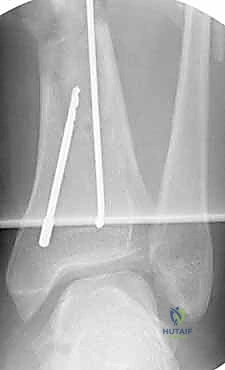

التسمير النخاعي لكسور الساق هو إجراء جراحي رائد لعلاج كسور عظم الساق (الظنبوب) عن طريق إدخال مسمار معدني داخل العظم لتثبيت الكسر. يوفر هذا العلاج استقرارًا قويًا، ويسرع الشفاء، ويقلل من المضاعفات، ويُعد الأستاذ الدكتور محمد هطيف في صنعاء خبيرًا رائدًا فيه.

الخلاصة الطبية السريعة: التسمير النخاعي لكسور الساق (Intramedullary Nailing) هو الإجراء الجراحي الأحدث، والأكثر أماناً، والأعلى فعالية لعلاج كسور عظم الساق (الظنبوب - Tibia). يعتمد هذا التدخل الجراحي الدقيق على إدخال مسمار معدني متطور (مصنوع من التيتانيوم أو الصلب الطبي المقاوم للصدأ) داخل التجويف النخاعي للعظم، مما يعمل كدعامة داخلية لتثبيت الكسر بصلابة فائقة. يوفر هذا العلاج استقرارًا ميكانيكيًا حيويًا ممتازاً، ويسرع من عملية الالتئام العظمي، ويقلل بشكل جذري من المضاعفات مقارنة بالطرق التقليدية القديمة كالجبس أو الشرائح الخارجية. يُعد الأستاذ الدكتور محمد هطيف، أستاذ جراحة العظام والمفاصل بجامعة صنعاء، الخبير الأول والرائد في هذا التخصص الدقيق في اليمن، حيث يجمع بين الخبرة الأكاديمية والسريرية التي تتجاوز 20 عامًا، واستخدام أحدث التقنيات الجراحية (مثل الجراحة الميكروسكوبية ومناظير المفاصل 4K) لضمان عودة المرضى لممارسة حياتهم الطبيعية بأقصى درجات الأمان والمصداقية الطبية.

ولكن مع التطور المذهل في الطب الحديث والهندسة الطبية الحيوية، برز التسمير النخاعي (Intramedullary Nailing) كالمعيار الذهبي (Gold Standard) لعلاج الأغلبية العظمى من كسور الساق. تعتمد هذه التقنية المتقدمة على إدخال مسمار معدني مجوف ومصمم هندسيًا ليتطابق تماماً مع الانحناءات الطبيعية للعظم.

باستخدام جهاز الأشعة السينية المتحرك داخل غرفة العمليات (C-arm Fluoroscopy)، يتم سحب الساق وإعادتها لوضعها التشريحي الصحيح (Reduction) دون فتح منطقة الكسر.

بعد ذلك، يتم إدخال سلك دليلي معدني رفيع داخل القناة النخاعية، يليه استخدام أدوات توسيع دقيقة (Reamers) لتنظيف وتوسيع القناة وتجهيزها لاستقبال المسمار. هذه الخطوة بحد ذاتها تحفز نمو العظم من خلال نشر الخلايا العظمية داخل القناة.

4. إدخال المسمار النخاعي والتثبيت النهائي

يتم تمرير مسمار التيتانيوم بدقة داخل العظم. وبمجرد التأكد من موضعه المثالي بالأشعة، يقوم البروفيسور هطيف بإدخال المسامير التشابكية (Locking Screws) العرضية في أعلى وأسفل المسمار لضمان التثبيت المطلق.